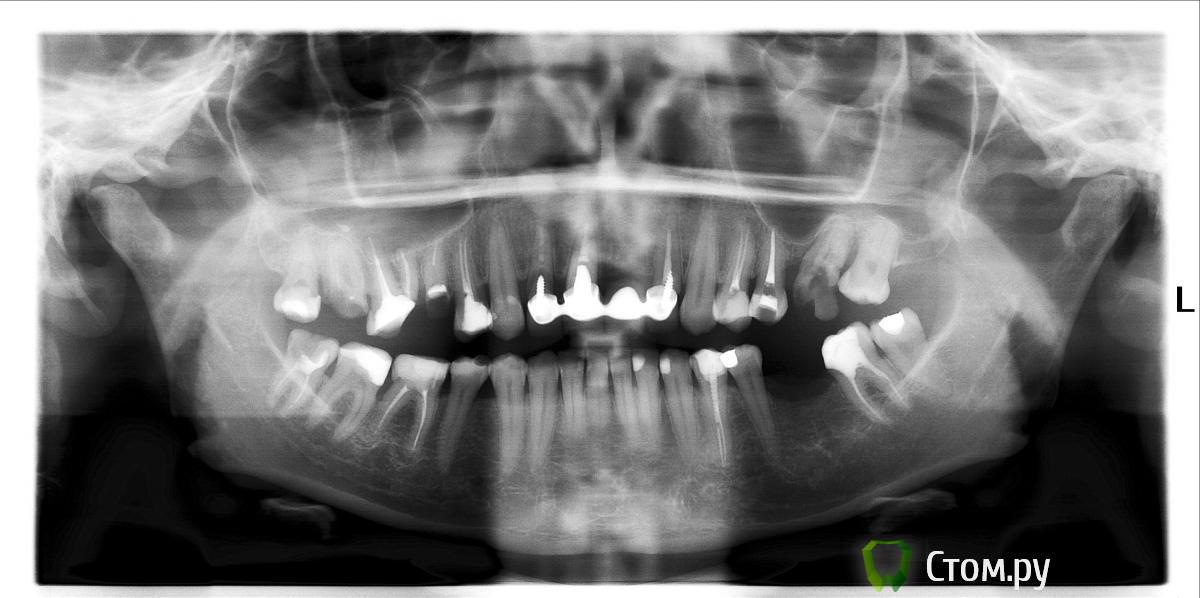

sssНаталия Опубликовано 10 ноября, 2011 Автор Поделиться Опубликовано 10 ноября, 2011 (изменено) Орто перед удалением. Зубы не запускала, всю жизнь лечусь, сколько себя помню. Коронки стояли с 12 лет, съёмный протез не рассматриваю - молодая ещё. Да и кость уйдёт. И так, говорят, нужно будет подсаживать. Удалили позавчера, теперь жду 3 месяца, потом пластика. Вот только не знаю, как врача выбирать - суперзвезду по деньгам не потяну, наверно, а ещё пугают, что передние сложно делать, да и подсаженная кость приживается, а потом рассасывается((. Врач, с которым я разговаривала, категорически не работает с искусственным материалом, только свою костную ткань пересаживает - а это, как я понимаю, повышает травматичность операции...Я понимаю, конечно, что во рту куча проблем и кроме фронта, и что нужно начинать с жевательных, но без передних зубов жить не получается в любом случае... Так что планирую сначала передние всё же.Сейчас депульпированы и обточены клыки, стоит временный мост. Врач, кстати, уверен, что мост с опорой на клыки - нормальная конструкция, и можно делать постоянный. Меня же терзают смутные сомнения... Изменено 10 ноября, 2011 пользователем sssНаталия Ссылка на комментарий

Bier Опубликовано 12 ноября, 2011 Поделиться Опубликовано 12 ноября, 2011 вместо резцов поставить 2 имплантата (позиции определить индивидуально),Удалять 18,17,16,15,27,48перелечить каналы 14,24,34,46зкоронки на 37, 34, 46, 14,13,23,24,25 имплантаты 17 и 15, 2 имплантата во фронте, 26, 36 возможно надо будет удалить и 28 и тогда будет еще 1 имплантат 27з. Ссылка на комментарий

Bier Опубликовано 14 ноября, 2011 Поделиться Опубликовано 14 ноября, 2011 да, там по снимку видно, что зуб сломался - это показание к удалению Ссылка на комментарий